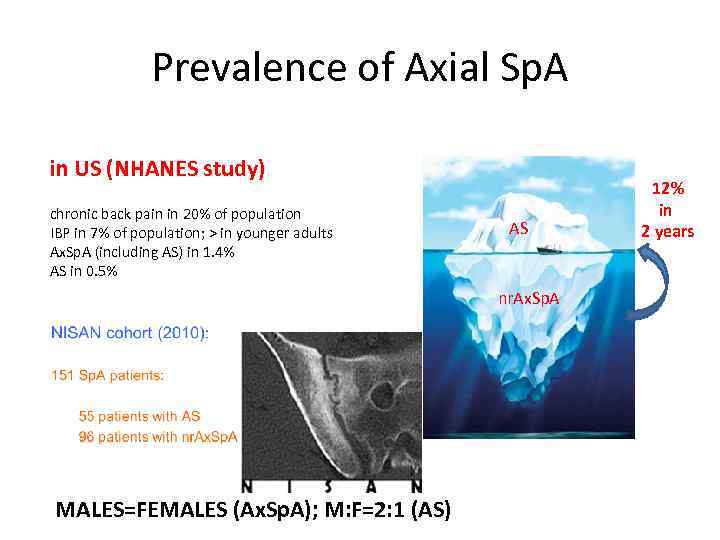

Prevalence of Axial Sp. A in US (NHANES study) chronic back pain in 20% of population IBP in 7% of population; > in younger adults Ax. Sp. A (including AS) in 1. 4% AS in 0. 5% AS nr. Ax. Sp. A MALES=FEMALES (Ax. Sp. A); M: F=2: 1 (AS) 12% in 2 years